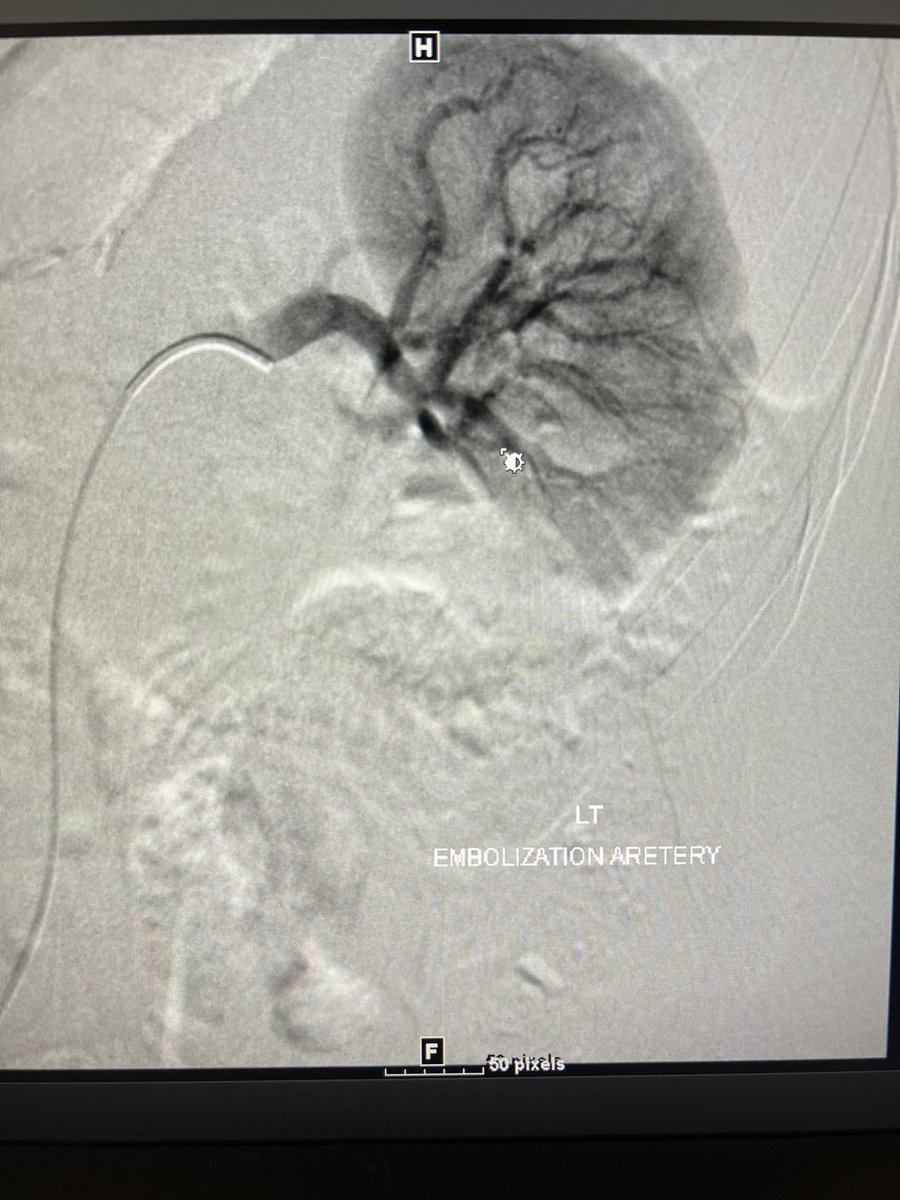

AVM embo with liquid. I luv what I do!!! Society of Interventional Radiology The Arab Journal of Interventional Radiology PAIRS CIRSE #avm #irad #ir #embo